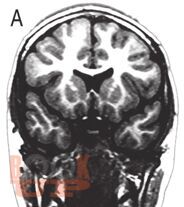

Чарльз Ньокиктьен известен как один из ведущих специалистов и основоположников нового научного направления - детской поведенческой неврологии - той области неврологии, которая изучает связь между проблемами в поведении и обучении и их неврологической основой. Впервые предлагаемый российскому читателю двухтомник обобщает современные данные неврологии и других нейронаук о развитии и отклонениях в развитии ребенка, а также неврологические и нейропсихологические методы их оценки.

Во II томе рассматриваются развитие памяти и внимания у детей и их расстройства, включая гиперактивное расстройство с дефицитом внимания, нарушения развития речи (дисфазия) и школьных навыков (дислексия, дисграфия, дискалькулия), аутистические расстройства, особые синдромы (поведенческие фенотипы), нейропсихиатрические нарушения, отставание и регресс в психомоторном развитии.